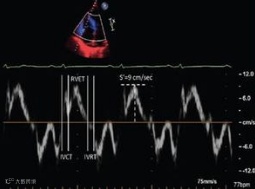

超声相控阵探头的中心频率 f=3MHz;回波灵敏度 S≥-50dB,-6dB 带宽 BW≥90%。相比传统 PZT(锆钛酸铅)陶瓷探头,具有高灵敏度、大带宽、高应用电压和宽的温度使用范围,可大幅提高医用超声成像的分辨率和穿透深度。

●应用前景:主要应用于高端医用超声成像与诊疗系统。具有自主知识产权,超声相控阵换能器性能指标达到国际先进、国内领先水平。